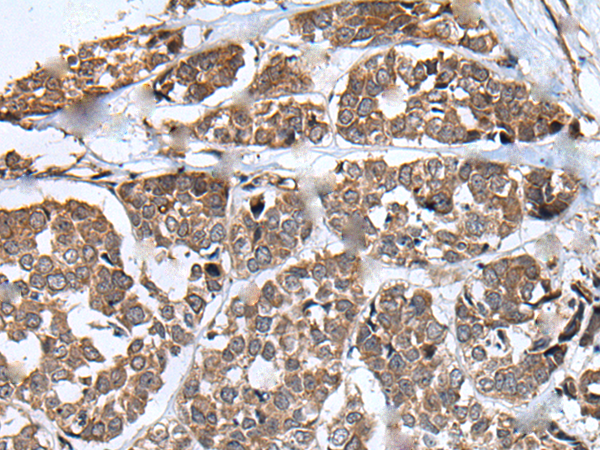

IHC positive control: |

Human colorectal cancer |

IHC Recommend dilution: |

25-100 |